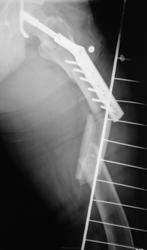

- https://radiomed.ru/sites/default/files/styles/case_slider_image/public/user/12/12.p2070031a.jpg?itok=rWDFsipj

Вы правы..., сейчас металлоостеосинтез будет проблемен.

красиво!!! DHSку теперь придется убрать, а вот что поставить? Ну может PFN, интрамедуллярный стержень с дополнительной фиксацией шейки. С б/берцовой проще, перелом благодатен для интрамедуллярного остеосинтеза.